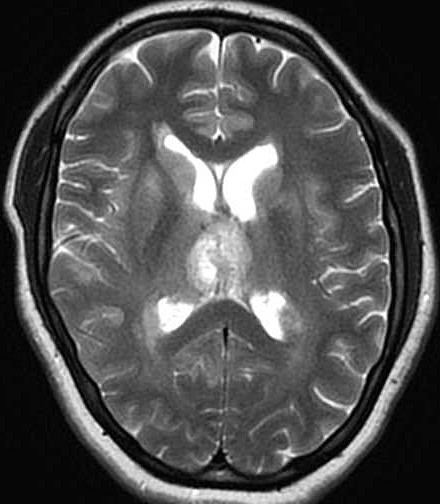

| Fem. 17a. |

| Nódulo sólido homogêneo preenchendo o III ventrículo, com limites precisos, com hipossinal em T1 e hipersinal em T2 e FLAIR, que se impregna por contraste paramagnético. Lesão menor implantada no assoalho do IV ventrículo provavelmente representa disseminação por via liquórica. |

| AXIAIS, FLAIR | T2 | |

| F. 17a. Tumor teratóide rabdóide atípico de III ventrículo. RM | HE | VIM, GFAP | HHF35, desmina, 1A4 | AE1AE3, EMA |